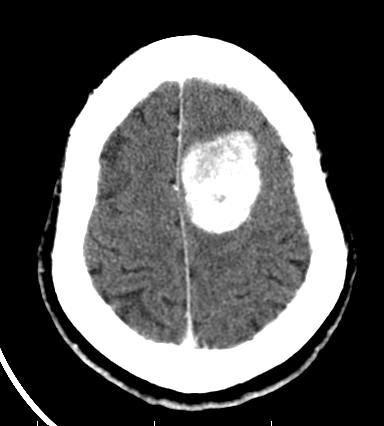

患者头痛头晕,门诊就诊。

脑膜瘤钙化,可以定期复查

钙化型脑膜瘤

就是脑膜瘤,位置表浅,钙化明显,外形光滑。